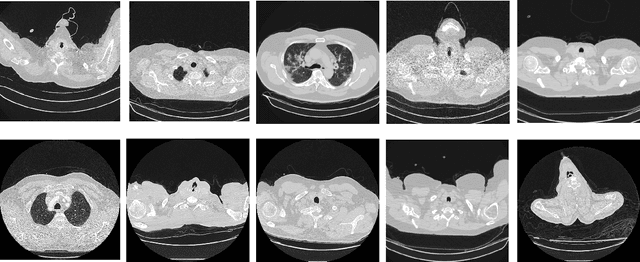

Abstract:The COVID-19 pandemic exposed critical limitations in diagnostic workflows: RT-PCR tests suffer from slow turnaround times and high false-negative rates, while CT-based screening offers faster complementary diagnosis but requires expert radiological interpretation. Deploying automated CT analysis across multiple hospital centres introduces further challenges, as differences in scanner hardware, acquisition protocols, and patient populations cause substantial domain shift that degrades single-model performance. To address these challenges, we present a heterogeneous ensemble of nine models spanning three inference paradigms: (1) a self-supervised DINOv2 Vision Transformer with slice-level sigmoid aggregation, (2) a RadImageNet-pretrained DenseNet-121 with slice-level sigmoid averaging, and (3) seven Gated Attention Multiple Instance Learning models using EfficientNet-B3, ConvNeXt-Tiny, and EfficientNetV2-S backbones with scan-level softmax classification. Ensemble diversity is further enhanced through random-seed variation and Stochastic Weight Averaging. We address severe overfitting, reducing the validation-to-training loss ratio from 35x to less than 3x, through a combination of Focal Loss, embedding-level Mixup, and domain-aware augmentation. Model outputs are fused via score-weighted probability averaging and calibrated with per-source threshold optimization. The final ensemble achieves an average macro F1 of 0.9280 across four hospital centres, outperforming the best single model (F1=0.8969) by +0.031, demonstrating that heterogeneous architectures combined with source-aware calibration are essential for robust multi-site medical image classification.

Abstract:COVID-19 has led to hundreds of millions of cases and millions of deaths worldwide since its onset. The fight against this pandemic is on-going on multiple fronts. While vaccinations are picking up speed, there are still billions of unvaccinated people. In this fight against the virus, diagnosis of the disease and isolation of the patients to prevent any spread play a huge role. Machine Learning approaches have assisted in the diagnosis of COVID-19 cases by analyzing chest X-rays and CT-scan images of patients. To push algorithm development and research in this direction of radiological diagnosis, a challenge to classify CT-scan series was organized in conjunction with ICCV, 2021. In this research we present a simple and shallow Convolutional Neural Network based approach, TeliNet, to classify these CT-scan images of COVID-19 patients presented as part of this competition. Our results outperform the F1 `macro' score of the competition benchmark and VGGNet approaches. Our proposed solution is also more lightweight in comparison to the other methods.